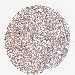

GLIOMA - Protein expressioni

A mouse-over function shows sample information and annotation data. Click on an image to view it in a full screen mode. Samples can be filtered based on level of antibody staining by selecting one or several of the following categories: high, medium, low and not detected. The assay and annotation is described here.

Note that samples used for immunohistochemistry by the Human Protein Atlas do not correspond to samples in the TCGA dataset.

Antibody stainingi

Antibody staining in the annotated cell types in the current human tissue is reported as not detected, low, medium, or high, based on conventional immunohistochemistry profiling in selected tissues. This score is based on the combination of the staining intensity and fraction of stained cells.

Each image is clickable and will lead to virtual microscopy that enables deeper exploration of all samples and also displays staining intensity scores, fraction scores and subcellular localization as well as patient and tissue information for each sample.

Antibody HPA039708

Antibody HPA040038

Staining

High

Medium

Low

Not detected

Intensity

Strong

Moderate

Weak

Negative

Quantity

>75%

75%-25%

<25%

None

Location

Nuclear

Cytoplasmic/membranous

Cytoplasmic/membranous,nuclear

Glioma, malignant, High grade

Glioma, malignant, Low grade